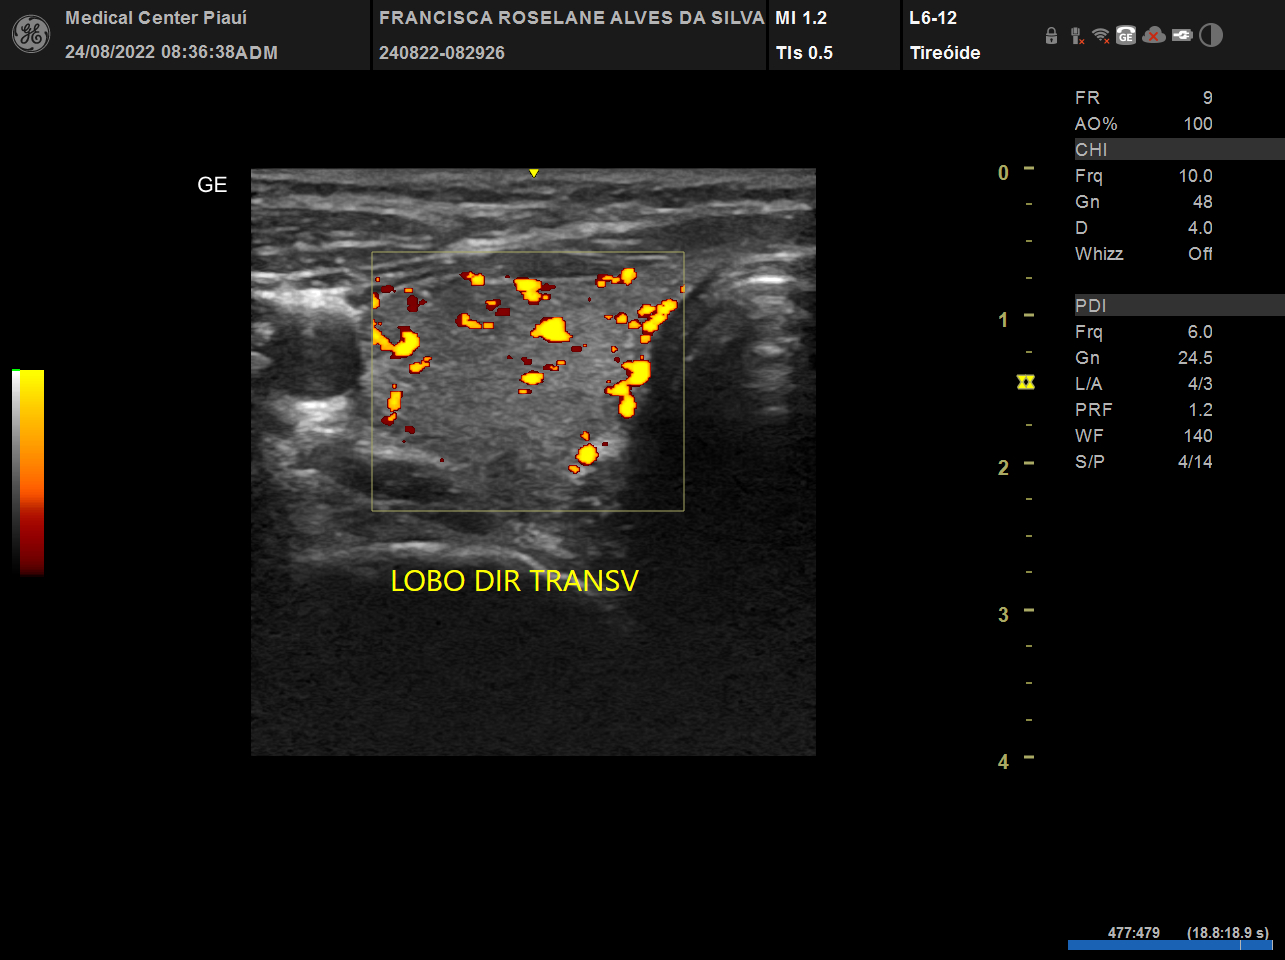

USG, TC e RN de tireoide